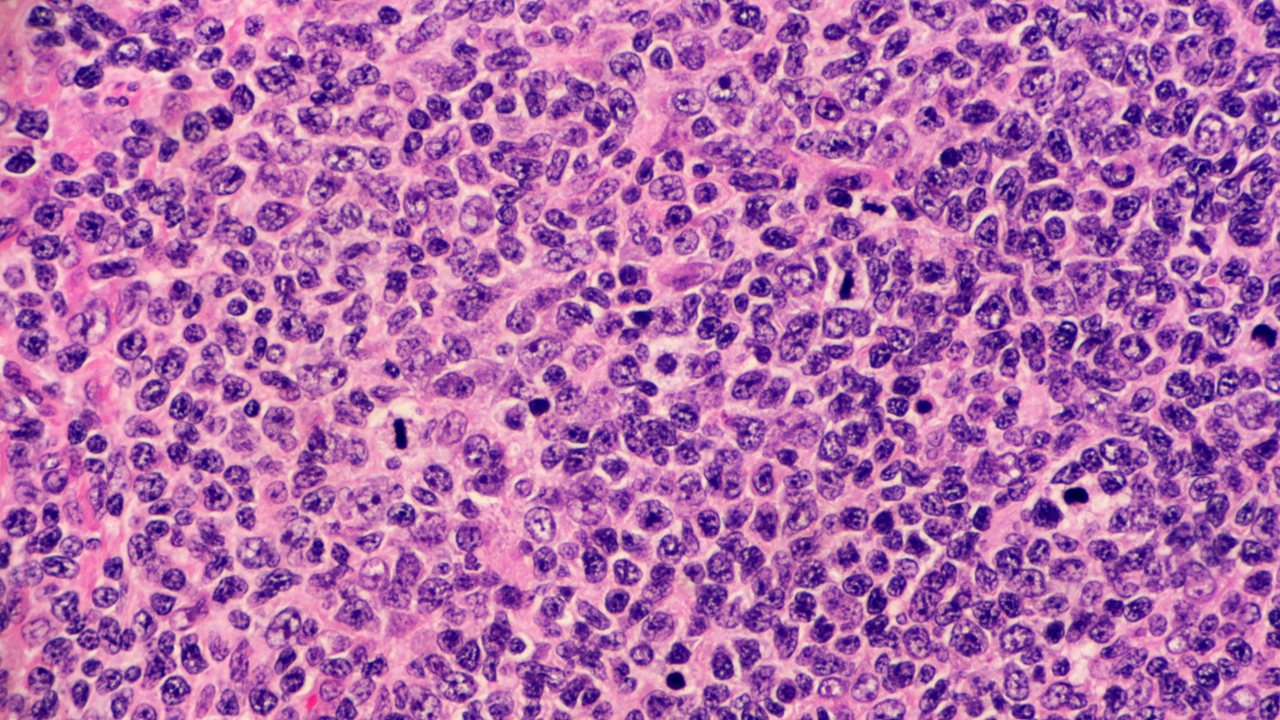

El LCBGD es el subtipo más común de linfoma no Hodgkin, caracterizado por su comportamiento agresivo. Aunque muchos pacientes responden al tratamiento de primera línea, aquellos con enfermedad refractaria o en recaída que no son candidatos a trasplante autólogo de células madre enfrentan una necesidad urgente de opciones terapéuticas más efectivas.